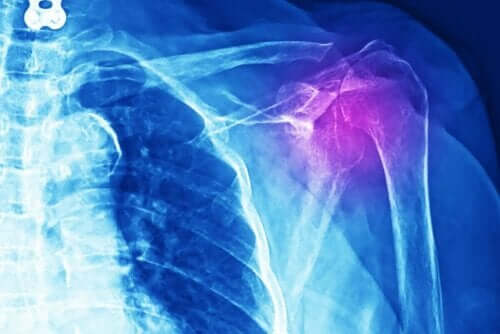

Olkapään jännetulehduksen selkein oire on tulehdus ja kipu. Henkilö saattaa tuntea aristusta liikutellessaan ja venyttäessään lihasta tai asettaessaan painoa nivelelle. Myös voima voi olla heikentynyt. Olkapään jännetulehdukselle tyypilliset tulehdus, kipu ja voiman puute rajoittavat henkilön kykyä suoriutua arjen askareista.

Lääkäreiden on tehtävä useita tutkimuksia diagnosoidakseen tämän vamman: tarpeeseen voivat tulla röntgenkuvat, ultraääni, magneettikuvaus tai tietokonetomografia. Lisäksi lääkärin on tehtävä fyysinen tutkimus ja perehdyttävä potilaan sairaushistoriaan.